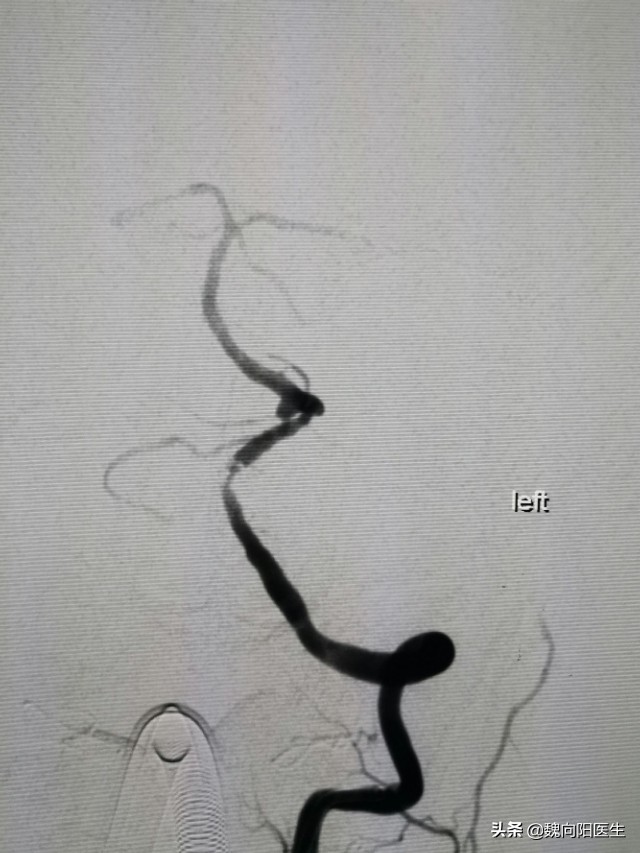

最好还是DSA说话:“右侧椎动脉闭塞,左侧椎动脉V3、V4段重度狭窄,后交通动脉发育不良。”

先给予近段狭窄部位,应用Gateway 2×9mm球囊扩张。

然后继续应用此球囊给予血管远端狭窄出扩张。

扩张之后狭窄病变明显好转,分别给予两狭窄处置入两枚支架(APPOLO 2.5×13mm和ENTERPRISE 4.5×22mm)。

再次造影:狭窄明显缓解。撤出导丝导管系统,手术结束。